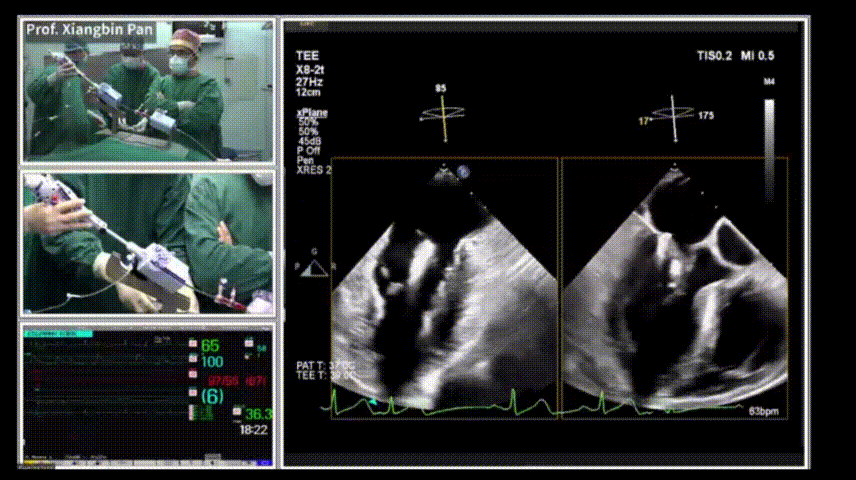

北京时间6月24日下午5:00,中国医学科学院阜外医院潘湘斌教授团队由中国北京向德国法兰克福正在举办的CSI(先天性、结构性和瓣膜性心脏病介入治疗大会)大会主会场转播了一例全超声引导下MitraClip 二尖瓣经导管缘对缘修复术(TEER),手术操作时间短且效果良好,有力展现了中国术者在TEER领域积累的经验和实力。

此前潘湘斌教授团队曾多次带领团队于国际心血管学术大会上进行全超声引导下不同类型介入手术转播,对于此次转播,潘湘斌教授表示:“这充分说明了我们中国原创的全超声引导下的介入手术是一套技术体系、一个方法学系统,可以用于攻克不同类型的疾病。”